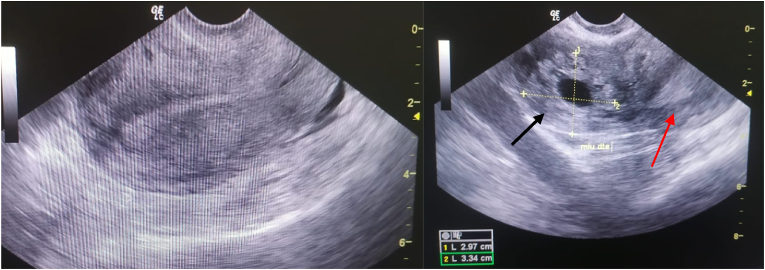

A 32-year-old patient, 2 gravida 1 para with a previous vaginal delivery, presented to the emergency department at 7 weeks of amenorrhea for pelvic pain. Clinical examination found a normal blood pressure with tachycardia at 130/min and a tender abdomen. The Bhcg level was 15,000 IU/L. Transvaginal ultrasound showed an empty uterus with a 30 × 33 mm gestational sac with no embryo, lateralized to the right, separated from the uterine cavity by a 3 mm myometrial rim, associated with a moderate intraperitoneal fluid effusion (Fig. 1). An emergency mini-laparotomy was indicated for suspicion of ruptured EP, which allowed the discovery of a hemoperitoneum with ruptured extra uterine pregnancy in the interstitial part of the right tube (Fig. 2). A cornuostomy with right salpingectomy was then successfully performed. Post operation recovery was uneventful.

Fig. 1.

Trasnvaginal ultrasound; left: absence of an intrauterine pregnancy on ultrasound. Right: eccentrically located gestational sac (black arrow) and the uterus (red arrow). (For interpretation of the references to colour in this figure legend, the reader is referred to the Web version of this article.)

The ultrasound finding was typical of interstitial pregnancy, including an eccentric gestational sac, surrounded by a myometrial rim, separated >1 cm from an empty uterine cavity [6]. Ackerman et al. also described the presence of an echogenic line, connecting the eccentric gestational sac with the endometrial cavity, representing the interstitial portion of the fallopian tube [5]. This sign was not found in our case, given the advanced gestational age of the pregnancy.